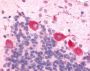

Applications IHC-P

IHC-P (6.8 µ, g/ml)